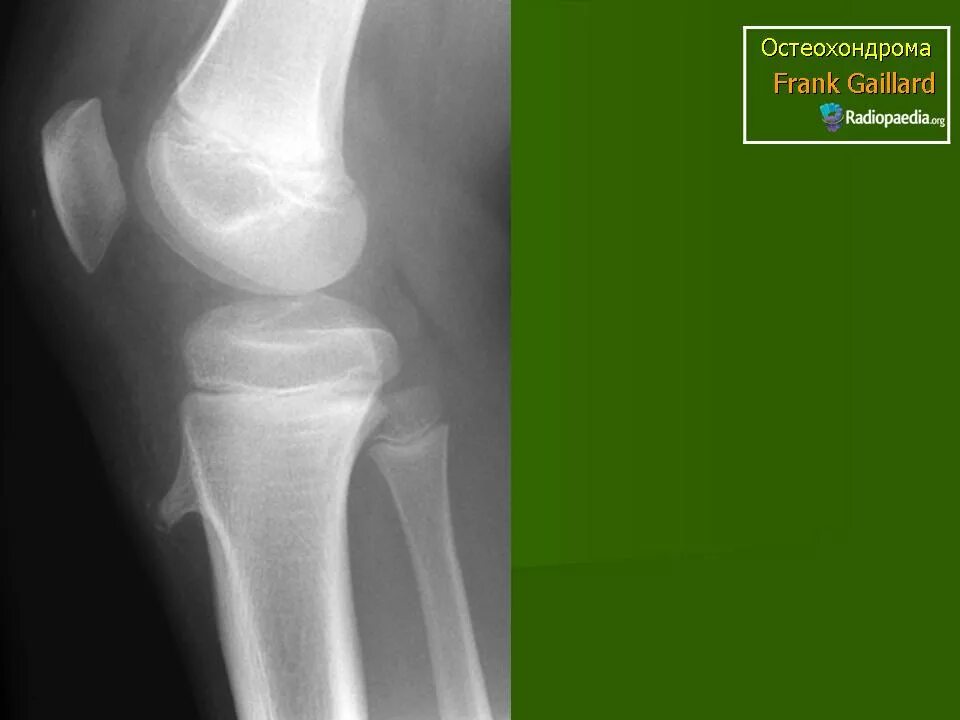

Экзостоз мкб 10